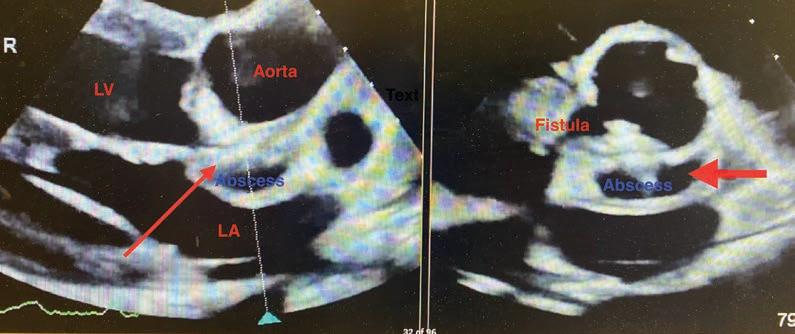

To coincide with the commencement of the National Lung Cancer Screening Program, ChestRad is bringing their sub-specialist service to Mandurah

ChestRad are specialists in Cardiac CT, Chest CT and Lung Cancer Screening

Cardiologists – Dr Edmund Brice, A/Prof Abdul Ihdayhid, A/Prof Chris Judkins, Dr Sam Tayeb, Dr Justin Teng and Dr Tashi Zhaxiduojie

Cardiothoracic radiologists – Dr Conor Murray and Dr Shriv Srigandan

ChestRad's rooms are at the Mandurah Specialist Centre on Minilya Parkway, Greenfields (near the Peel Health Campus) All rebatable Mandurah services BULK BILLED! www.chestrad.com.au